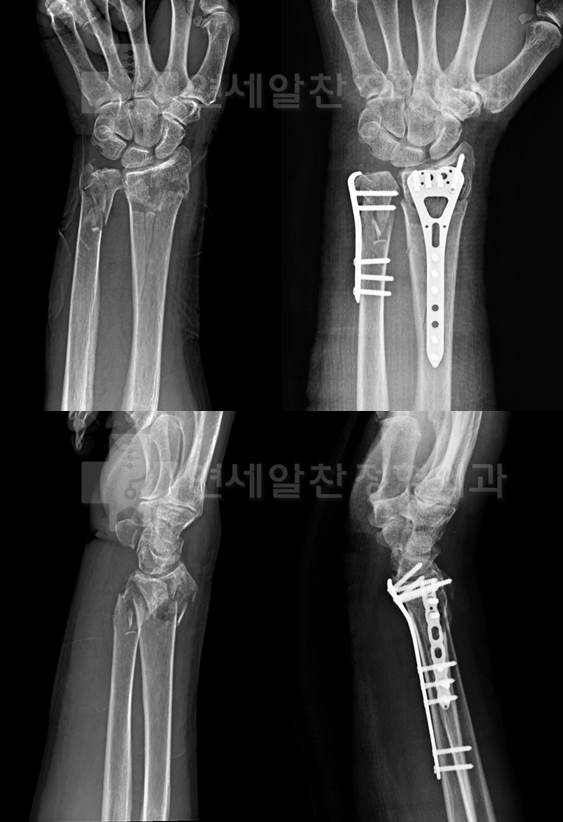

원위 요골 및 척골의 복잡 골절에 대한 관혈적 정복술 및 금속 내고정술의 결과

겨울철이 되니 낙상에 의한 외상이 많아 진다. 75세 여자 환자로 빙판길에서 넘어지고 난 후 응급실을 내원...

2017. 12. 27.